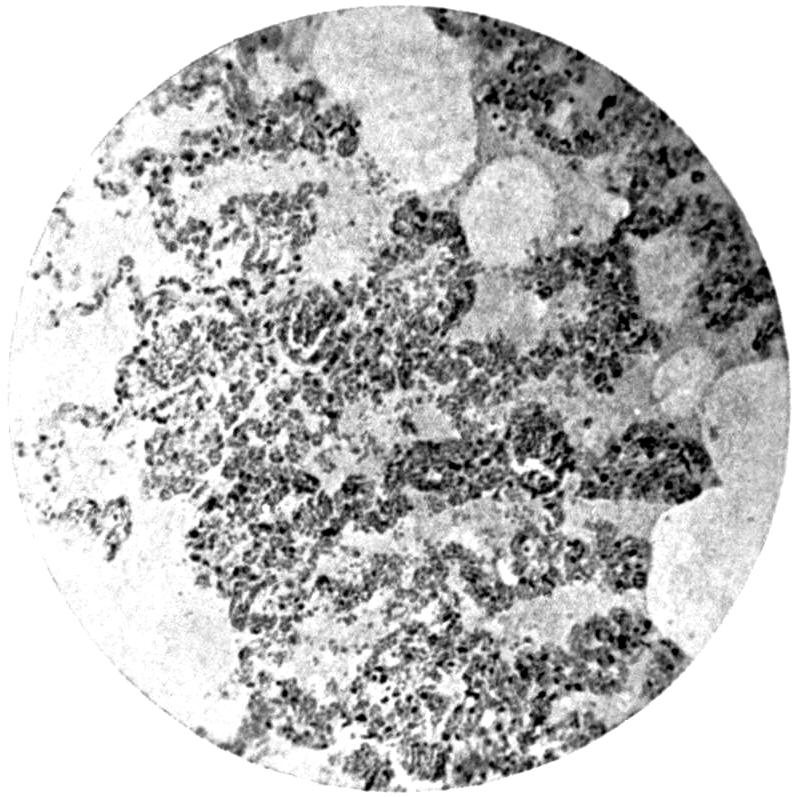

Plate II. 93